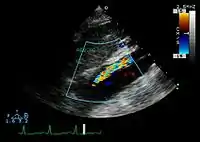

Ultrasound

The transesophageal echocardiogram (TEE) is a good test in the diagnosis of aortic dissection, with a sensitivity up to 98% and a specificity up to 97%. It has become the preferred imaging modality for suspected aortic dissection. It is a relatively noninvasive test, requiring the individual to swallow the echocardiography probe. It is especially good in the evaluation of AI in the setting of ascending aortic dissection, and to determine whether the ostia (origins) of the coronary arteries are involved. While many institutions give sedation during transesophageal echocardiography for added patient comfort, it can be performed in cooperative individuals without the use of sedation. Disadvantages of TEE include the inability to visualize the distal ascending aorta (the beginning of the aortic arch), and the descending abdominal aorta that lies below the stomach. A TEE may be technically difficult to perform in individuals with esophageal strictures or varices.